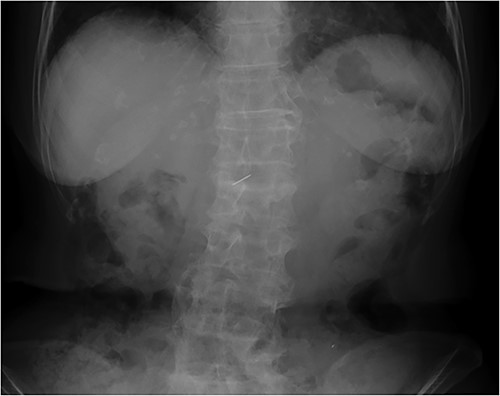

An 81-year-old woman presented to our hospital with an abnormal shadow on her abdominal X-ray performed during a gastrointestinal checkup. She had no subjective symptoms. She had no comorbidities other than hypertension and no history of laparotomy. Her vital signs were normal. No foreign body was palpable on the abdominal wall, chest wall, or back. No mental abnormality or cognitive impairment was noted. A plain abdominal radiograph showed a needle-like shadow at the second lumbar vertebra level (Fig. 1). Abdominal computed tomography (CT) displayed a needle-like shadow obliquely directed from the inferior surface of the liver to the lateral segment. No intrahepatic or intraperitoneal abscess was observed (Fig. 2). Upper gastrointestinal endoscopy revealed no stomach or duodenal ulcer scarring. Detailed history revealed no history of trauma or acupuncture treatment and no memory of accidental ingestion of needles. No subjective symptoms such as sore throat or epigastric pain were reported. Based on these findings, a sewing needle was accidentally swallowed without awareness, perforating at the pylorus of the stomach or duodenal bulb and straying into the liver. The patient had no symptoms at the time of the visit, and we told her that she could be followed up. However, the patient strongly desired needle removal; therefore, we decided to perform a laparoscopic resection. Laparoscopic observation revealed fibrous adhesion between the lesser curvature of the gastric pylorus and the inferior surface of the outer hepatic segment. When the adhesion was detached, the foreign body tip was observed on the subhepatic surface. It was grasped with forceps, extracted, and removed from the abdominal cavity (Fig. 3). A sewing needle of ~3-cm length was removed (Fig. 4). The patient had a good postoperative course and was discharged from the hospital on postoperative Day 4 without any complications.

Plain abdominal radiograph displaying a needle-like metallic shadow at the second lumbar vertebral level.